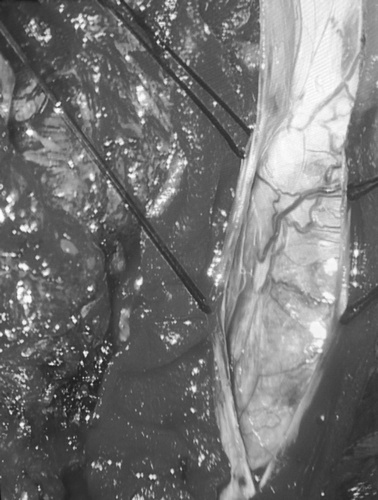

手术由郑州大学五附院神经外科带头人王新军教授主刀,由神经外科二病区主任单峤主任医师、吴建珩副主任医师和王振主治医师组成的医疗团队协同实施。术中发现肿瘤质地不均,同脊髓粘连较重,并浸润包裹多支脊神经根。此时大家都屏住了呼吸,手术室里只能听见心电监护的滴答声,而一场与肿瘤惊心动魄的战斗已在显微镜下悄然打响。切皮、显露、细致分离、切除肿瘤、保护脊髓,一切都井然有序。经过3个多小时的显微手术,终于将长达15厘米跨越5个脊髓节段的巨大肿瘤全部切除,完好无损地保护了患者的脊髓和脊神经的功能,手术取得了圆满成功!

镜下肿瘤照片